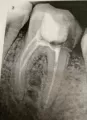

Стал беспокоить зуб под пломбой, на пломбе была трещина. Пошла к стоматологу, оказалось глубокий кариес под пломбой, поставила новую пломбу. После этого зуб стал болеть, больно при надкусывании. Пришла опять к стоматологу, сказала, давайте опять пломбу поменяем. Оказалось, что она в прошлый раз не до конца дочистила, там был еще кариес. Поставила пломбу, надкусывать не больно стало, но зуб побаливать. Пришла опять, сказала депульпировать надо. Почистила каналы, поставила временную пломбу. Вот вчера запломбировала каналы. Сделала снимок. Стоматолог сказала, что каналы запломбированы хорошо. Но мне кажется, что как будто не до конца они запломбированы, по снимку.

Хорошо ли запломбированы каналы?

Действительно возможно, что канал не до конца запломбирован.